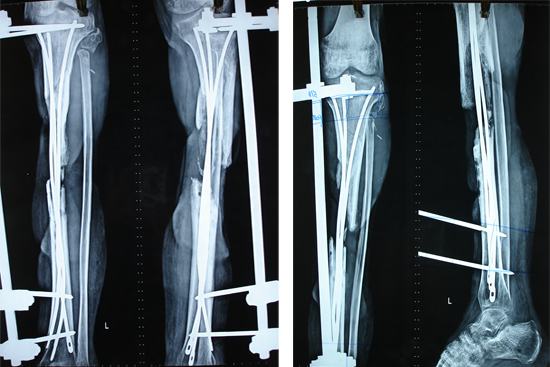

Tibialisation Of Fibula